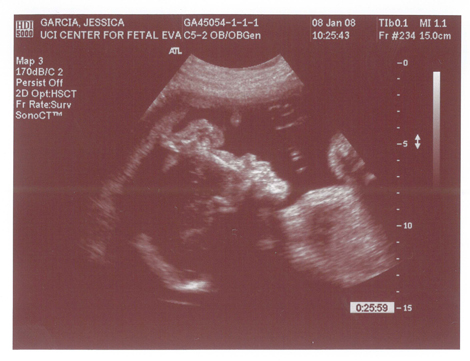

Babies First Pictures!!! ITS A BOY!

Yes we got a new dsmer coming into the world soon. We got our ultrasound today and its gonna be a boy. And shes a lot further along then we had originally thought. Shes due on April 15th which puts her at almost 6.5 months, (and really not showing it.) He weighs currently ~2lbs. He even opened his mouth while on camera which was really cool.

Here are the pics.

Pic 1: The babies head profile

Pic 2: Mouth is open!